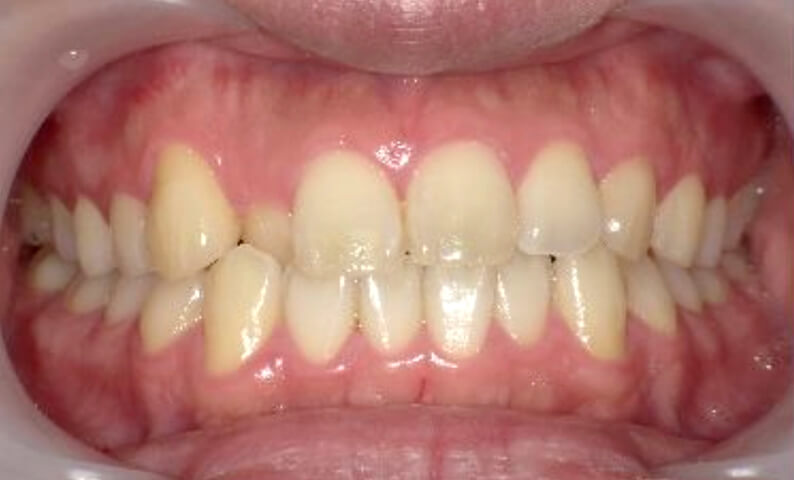

症例_025 上下顎の部分矯正

治療期間:13ヶ月金額:51万円+税女性前歯のガタガタ出っ歯

| Before | After |

|---|---|

|